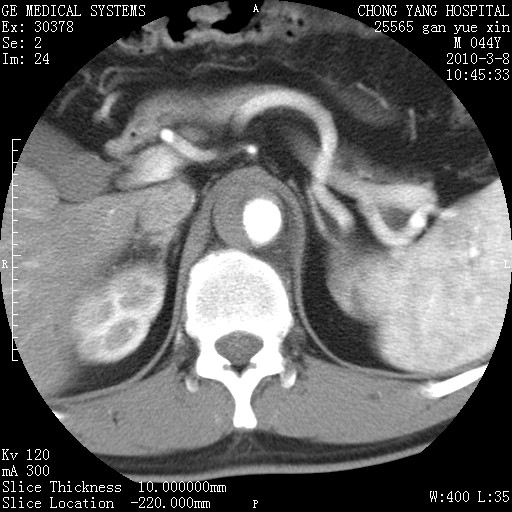

标题: CT24940:主动脉增强,典型病例。 [打印本页]

标题: CT24940:主动脉增强,典型病例。

夹层动脉瘤。

夹层动脉瘤,典型

主动脉夹层。

动脉夹层的分型:

⒈debakey分型:根据主动脉夹层累及部位,分为三型:ⅰ型:原发破口位于升主动脉或主动脉弓部,夹层累及升主动脉、主动脉弓部、胸主动脉、腹主动脉大部或全部,少数可累及髂动脉。ⅱ型:原发破口位于升主动脉,夹层累及升主动脉,少数可累及部分主动脉弓。ⅲ型:原发破口位于左锁骨下动脉开口远端,根据夹层累及范围又分为ⅲa,ⅲb。ⅲa型:夹层累及胸主动脉。ⅲb型:夹层累及升主动脉、腹主动脉大部或全部。少数可累及髂动脉。

⒉stanford分型:a型:夹层累及升主动脉,无论远端范围如何。b型:夹层累及左锁骨下动脉开口以远的降主动脉。

夹层动脉瘤,少量胸水

夹层动脉瘤;左侧少量胸腔积液。